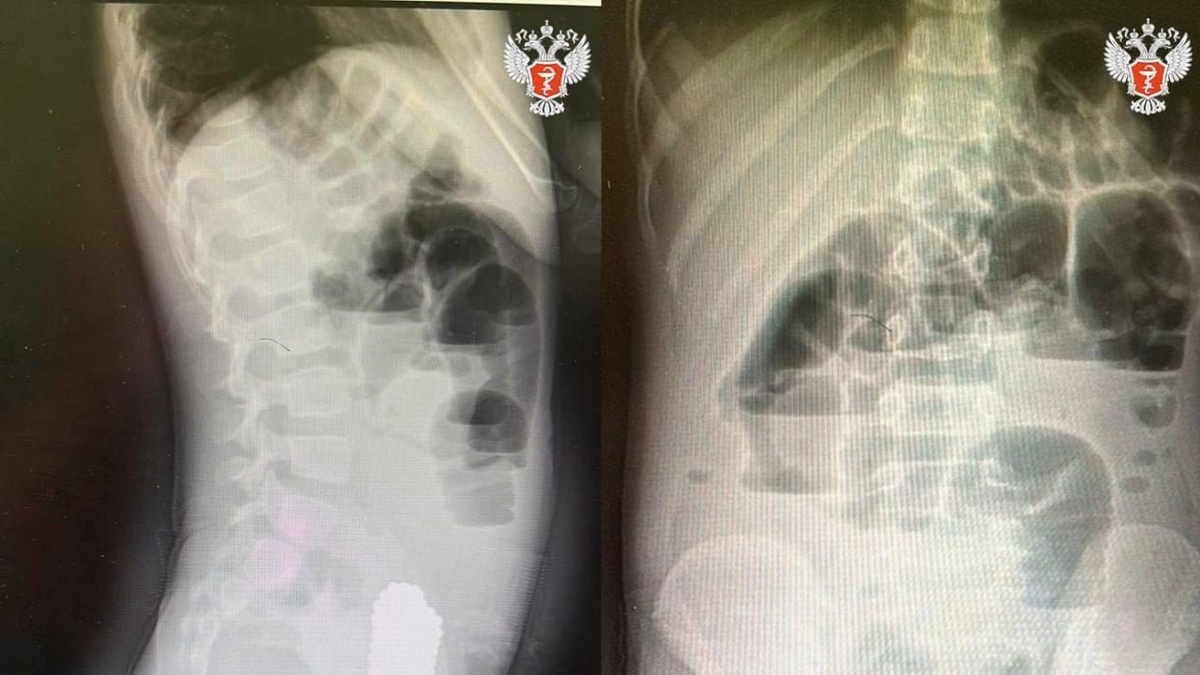

Волгоградские врачи спасли девочку, проглотившую 134 магнитных шарика

Ребёнка доставили в больницу с симптомами ОРВИ, но обследование выявило кишечную непроходимость. Хирурги провели срочную лапароскопию и извлекли опасный ком из магнитов. Девочка восстанавливается после операции. Медики напоминают об опасности мелких деталей в детских играх.